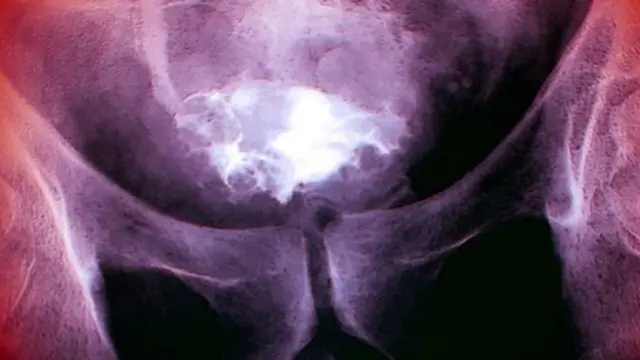

तस्बिर स्रोत, Science Photo Library